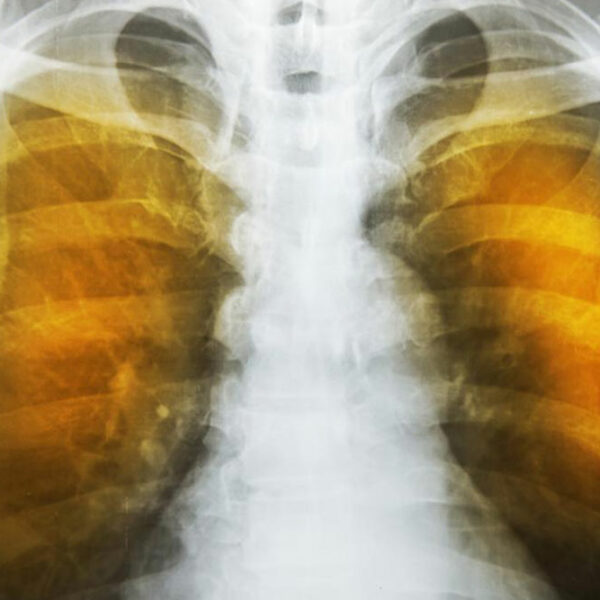

The symptoms of emphysema are exceedingly severe and cause considerable damage to the lungs before the symptoms even show up. Generally, one feels a lack of energy and the tendency to skip some of the common daily routines. It progresses from slight difficulty in breathing to wheezing and then to a persistent cough that does not go away. One starts to feel a tightness in the chest and feels short of breath on exertion. Tiredness and persistent cough become constant.

Infections can set in, turning the sputum yellow, which also leads to loss of appetite, further aggravating tiredness. One will lose sleep and even sexual function. All this constant suffering and ill health lead to depression which would in turn lead to the patient needing psychiatric help. The lips and fingernails turn blue or gray due to lack of oxygen in the blood. One may get into a condition called hypoxia and may have to resort to oxygen therapy.

As the deterioration continues, the alveoli lose their strength and start rupturing. In extreme cases, there may be large scale destruction which leads to empty spaces in lungs called bullae. This would reduce the functional area of the lung which in extreme cases call for surgical removal. In an extremely rare condition, large scale rupture of alveoli can cause a condition called pneumothorax and the collapse of the lung, a very serious condition, which can be fatal. The best thing one can do is stop exposure to irritants.